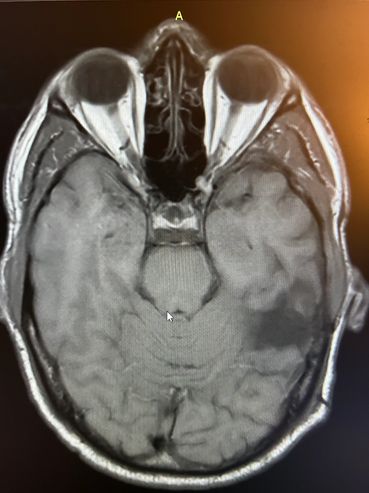

Axial MRI scan showing detailed brain structures including eye sockets and brain tissue.